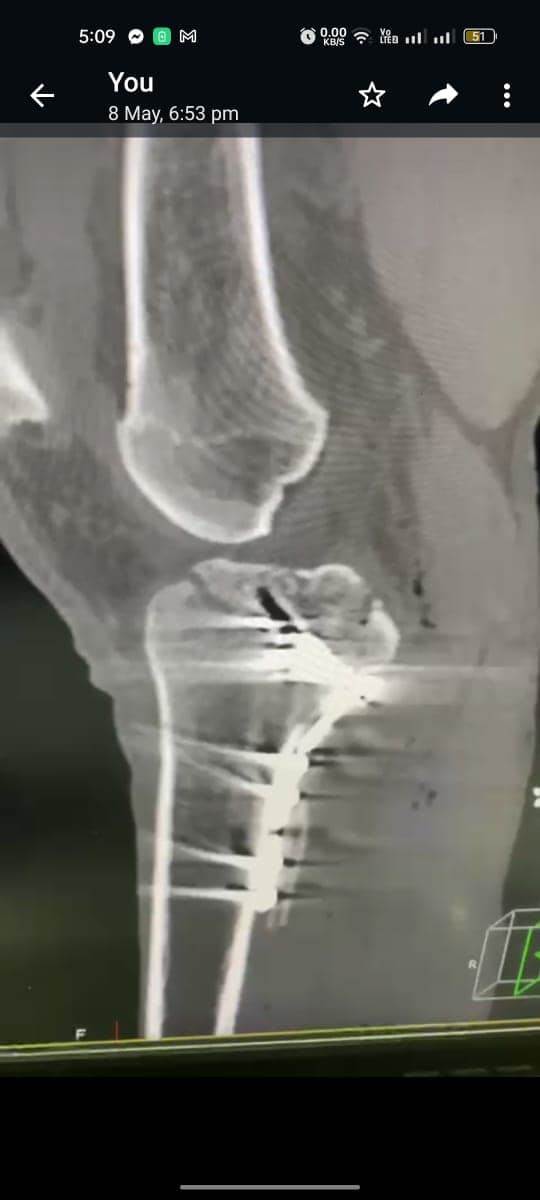

مشيرًا الى أن ذلك النوع من الكسور يكون قريبًا جدًا من الأعصاب والأوعية الدموية الرئيسية للساق والتي توجد خلف مفصل الركبة.. حيث تم الوصول الى الكسر وإعادة بناء سطح المفصل وتثبيته باستخدام شريحة ومسامير وأسلاك معدنية باستخدام جرح ٧ سنتيمترات خلف الركبة واستخدام مسامير جانبية مجوفة بدون فتح لتثبيت الجزء الخارجى من سطح المفصل، وتم الاطمئنان على الأوعية الدموية قبل إفاقة المريض، وبعد تمام الإفاقة.. تم الاطمئنان على الأعصاب والأوعية للمريض.

وأضاف أنه نظرًا لقرب هذا الكسر من سطح المفصل تم عمل أشعة مقطعية بعد الجراحة للتأكد من جودة بناء المفصل وعدم وجود أى بروز للمسامير داخل المفصل، وجارٍ تحضير المريض لعمل رنين مغناطيسى لتحديد الأربطة الداخلية والخارجية للركبة التي ستحتاج لإعادة بناء بالمنظار.